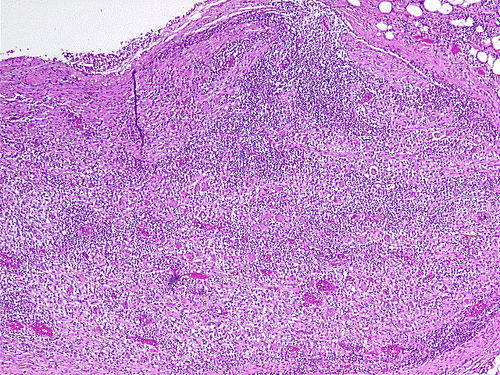

The overall tissue preservation is less than optimal because of postmortem autolysis. Panel A and B are taken from the cerebellum. The molecular layer, Purkinje cell layer, and internal granular layer are included (Panel A). Solitary eosinophilic intracytoplasmic inclusions of variable size are present in the Purkinje cells. No inflammatory cell infiltration is present in the cerebellum. The vacuolar spaces (Panel B) is partly due to autolysis and partly due to hypoxic/ischemic changes. Pyramidal cells in the hippocampus (Panel C), cortical neurons in parietal lobe (Panel D) and other neocortical areas adopted an elongated and contracted contour with loss of nuclear details. These are histologic features consistent with hypoxic/ischemic changes. Similar to the cerebellum, solitary eosinophilic cytoplasmic inclusion bodies are present and there is no inflammatory cell infiltration. Multiple eosinophilic cytoplasmic inclusion bodies within a single neuron are occasionally found. Some of these neurons containing multiple inclusions from the substantia nigra are illustrated in Panel E. Although inflammatory cell infiltration is scant in the cerebrum and cerebellum, perivascular chronic inflammatory cell infiltrations are common in the medulla (Panel F and G), in the paravertebral sympathetic ganglion (Panel H and I) and in the spinal cord (not shown). Intracytoplasmic inclusions, however, are not found in the medulla, spinal cord, and paravertebral sympathetic ganglion. Under the electron microscope, rod-shape or bullet-shaped viral particles are found (Panel J).

The brain and spinal cord may appear swollen but are usually free of focal lesions. Histopathologically, rabies is a widespread polioencephalomyelitis. Leptomeningeal and parenchymal perivascular lymphocytic infiltrations are usually present but often not intense. Neuronophagia can also be seen. The amount of inflammation of the case under discussion is, in fact, on the intense side of the scale. The pathognomonic Negri bodies 10, 11, 12 are sharply delineated, round to oval, eosinophilic, neuronal cytoplasmic inclusions; first described by Negri in 1903 10. These inclusions are often solitary but may also be multiple in a single neuron. Lyssa bodies refer to less well delineated and more pleomorphic neuronal cytoplasmic viral inclusions. Babes’ nodules refer to clusters of microglia that remain after destruction of neurons. When immunohistochemistry is employed, the distributions of viral antigen are far more extensive than that estimated by conventional light microscopy 13. Negri body and rabies viral antigen as demonstrated by immunohistochemistry are most commonly seen in large neurons of the hippocampus (Pyramidal cells), cerebellum (Purkinje cells), thalamus, basal ganglia, cerebral cortex and in the brain stem, especially gray matter of the pons and medulla. They are also found in spinal cord motor neurons and dorsal root ganglion, especially in the paralytic form.  Immunohistochemistry also demonstrated rabies viral antigen in astrocytes and oligodendrocytes 13. Characteristically, a striking discrepancy between the degree of inflammation and amount of inclusion bodies is observed, as in our case, in many cases.